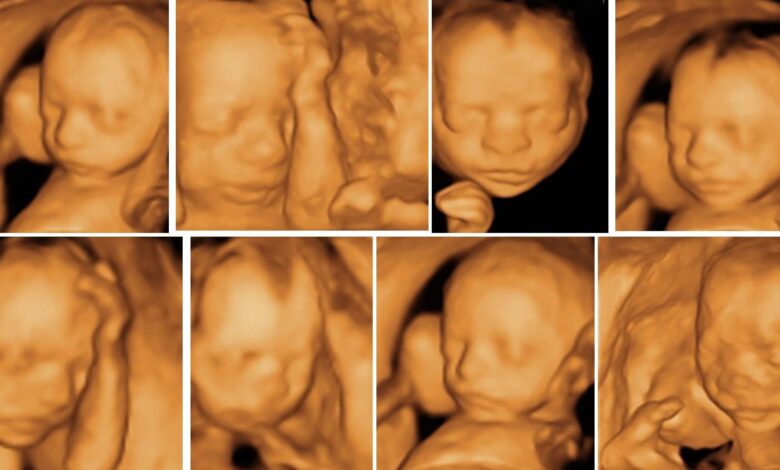

• أشعة السونار (Ultrasound): وتحديداً قياس “السمك القفوي” (NT Scan) في الفترة ما بين الأسبوع الـ 11 والـ 14 من الحمل. زيادة هذا القياس قد تشير لزيادة احتمالية الإصابة بمتلازمة داون.